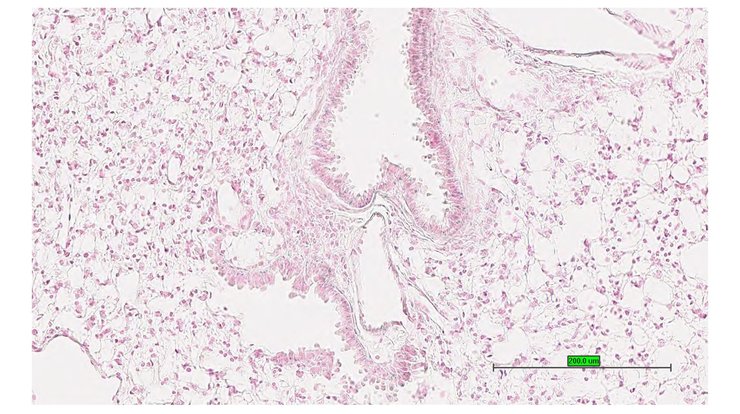

TS28: lung Present UC Davis_1886666

Specimen UC Davis_1886667: postnatal adult; Ncoa5tm1.1(KOMP)Mbp/Ncoa5+ (more )

Structure Level Pattern Image Note

TS28: lung Present UC Davis_1886667

TS28: lung Present UC Davis_1886733

Specimen UC Davis_1886734: postnatal adult; Ncoa5tm1.1(KOMP)Mbp/Ncoa5+ (more )

TS28: lung Present UC Davis_1886734